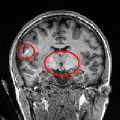

To further investigate the smoothing effect of our reconstruction algorithm, gray matter interface of the cortical surface has bee extracted using the above mentioned BrainVISA pipeline. Extracted surfaces (medial and lateral views) from mSENSE and 3D-UWR-SENSE images are show in Fig. 3 for . For comparison purpose, we provide results with mSENSE at as ground truth.

For the lateral view, one can easily conclude that extracted surfaces are very similar.

However, the medial view shows that mSENSE is not able to correctly segment the brainstem (see right red ellipsoid in

the mSENSE medial view). Moreover, results with mSENSE are more noisy compared to 3D-UWR-SENSE (see left red ellipsoid

in the mSENSE medial view). In contrast, the calcarine sulcus is slightly less accurately extracted with

our approach.

It is also worth noticing that similar results have been obtained on 14 other subjects.